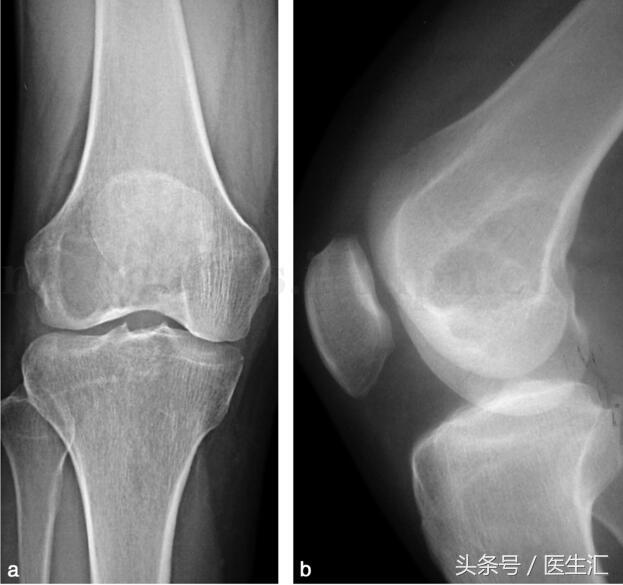

影像學(xué)檢查:X 線示右股骨遠(yuǎn)端骨端發(fā)生的一個(gè)偏心、基質(zhì)均勻、皮質(zhì)膨脹、皮質(zhì)無骨破壞、無骨膜反應(yīng)、無軟組織腫塊的溶骨性破壞(圖29‐1a,圖29‐1b)。CT 示右股骨遠(yuǎn)端骨端的溶骨性破壞,基質(zhì)均勻,注射造影劑后,病變強(qiáng)化,CT 值由強(qiáng)化前的40HU 增加到強(qiáng)化后的110HU(圖29‐2a~圖29‐2c)。

圖29‐1

a﹒右股骨下段外髁部溶骨性骨破壞(X 線正位片);b﹒右股骨下段外髁部溶骨性骨破壞(X 線側(cè)位片)